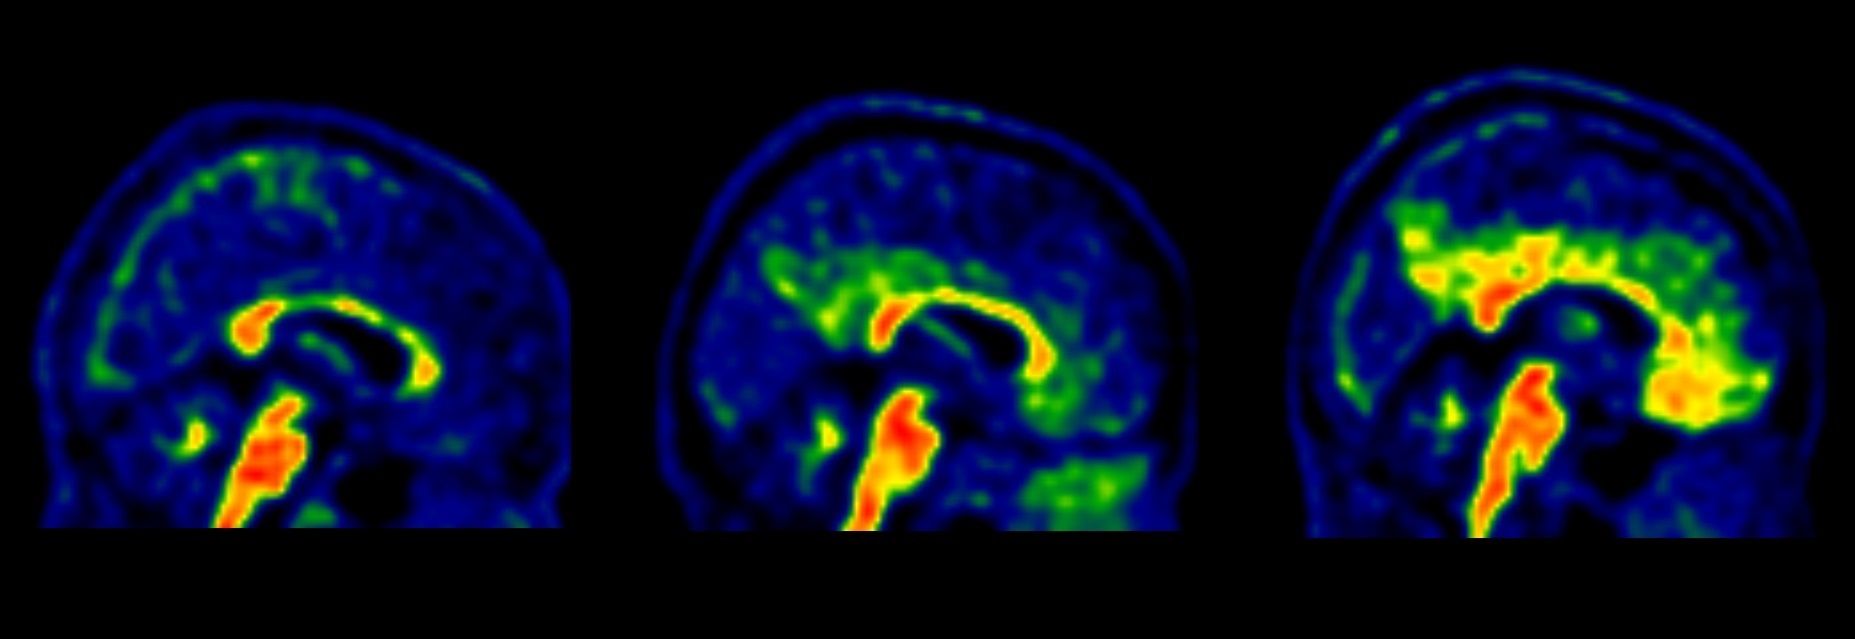

Un estudio liderado por Fundación ACE, Instituto Catalán de Neurociencias Aplicadas y financiado por Fundación Bancaria "la Caixa", Grifols, Fundación ACE y el Instituto de Salud Carlos III, ha identificado tres categorías de genes implicados con la enfermedad de Alzheimer.

El proyecto, que cuenta con la colección de muestras de Alzheimer más grande del mundo recogidas en un único centro desde 2004, se conoce como 'GR@ACE' (Genomic Research At Fundació ACE), y ha analizado durante su primera fase el genoma de 12.368 personas, 6.063 de ellas con demencia tipo Alzheimer.